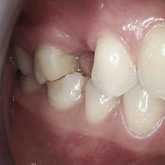

We make it a priority to incorporate the latest in dental technology in everything we do at our practice. ...